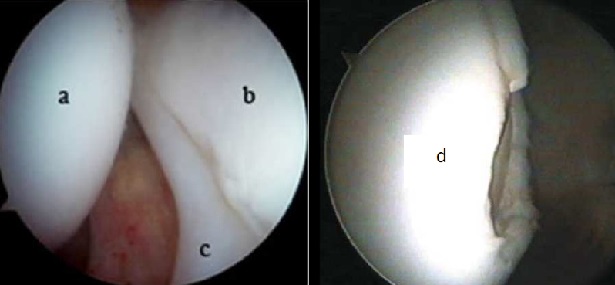

Negli stadi di osteonecrosi ove è già presente un danno condrale dovuto all’infarto osseo è neccessario associare il tempo di riparazione articolare.

Tale procedura artroscopica deve essere eseguita da un chirurgo esperto che riconosca la migliore tecnica di medicina rigenerativa da applicare e che possa inoltre ridurre al minimo il tempo chirurgico.

Tramite due accessi di circa 1 cm si visualizza direttamente la cartilagine articolare, il labrum acetabolare e le lesioni.

Le procedure applicabili hanno l’obiettivo di regolarizzare e riparare i danni per preservare l’articolazione e diminuire il dolore.

In base alla sede della lesione, alle dimensioni ed alle caratteristiche del paziente varie tecniche di medicina rigenerativa vengono infine applicate per determinare uno stimolo biologico riparativo sia all’osso subcondrale che al danno cartilagineo.